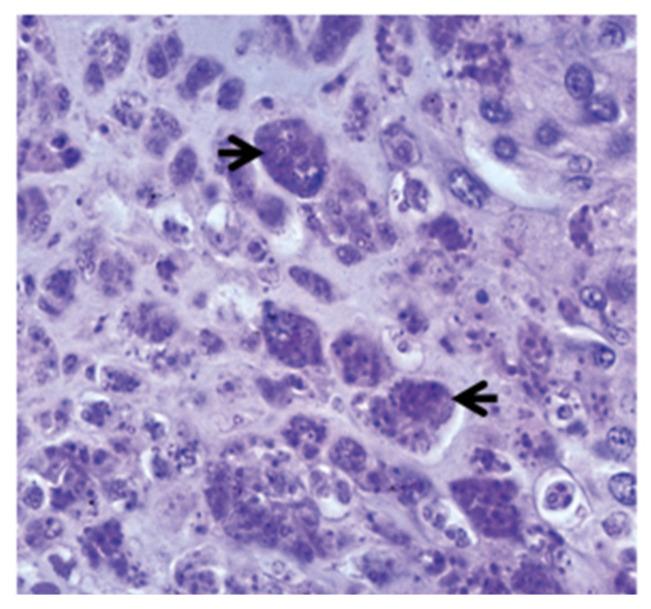

Salmonids are affected by the economically significant whirling disease (WD) caused by the myxozoan parasite . In the past, it was endemic to Eurasia, but it has now spread to different regions of North America, Europe, New Zealand, and South Africa. Among salmonids, rainbow trout is considered the most highly susceptible host. Upon entering to the host's body, the parasite invades the spine and cranium, resulting in whirling behaviour, a blackened tail, and destruction of cartilage. The disease is characterized by the infiltration of numerous inflammatory cells, primarily lymphocytes and macrophages, with the onset of fibrous tissue infiltration. Several efforts have been undertaken to investigate the role of various immune modulatory molecules and immune regulatory genes using advanced molecular methods including flow cytometry and transcriptional techniques. Investigation of the molecular and cellular responses, the role of STAT3 in Th17 cell differentiation, and the inhibitory actions of suppressors of cytokine signaling (SOCS) on interferons and interleukins, as well as the role of natural resistance-associated macrophage proteins (Nramp) in WD have significantly contributed to our understanding of the immune regulation mechanism in salmonids against . This review thoroughly highlights previous research and discusses potential future directions for understanding the molecular immune response of salmonids and the possible development of prophylactic approaches against WD.